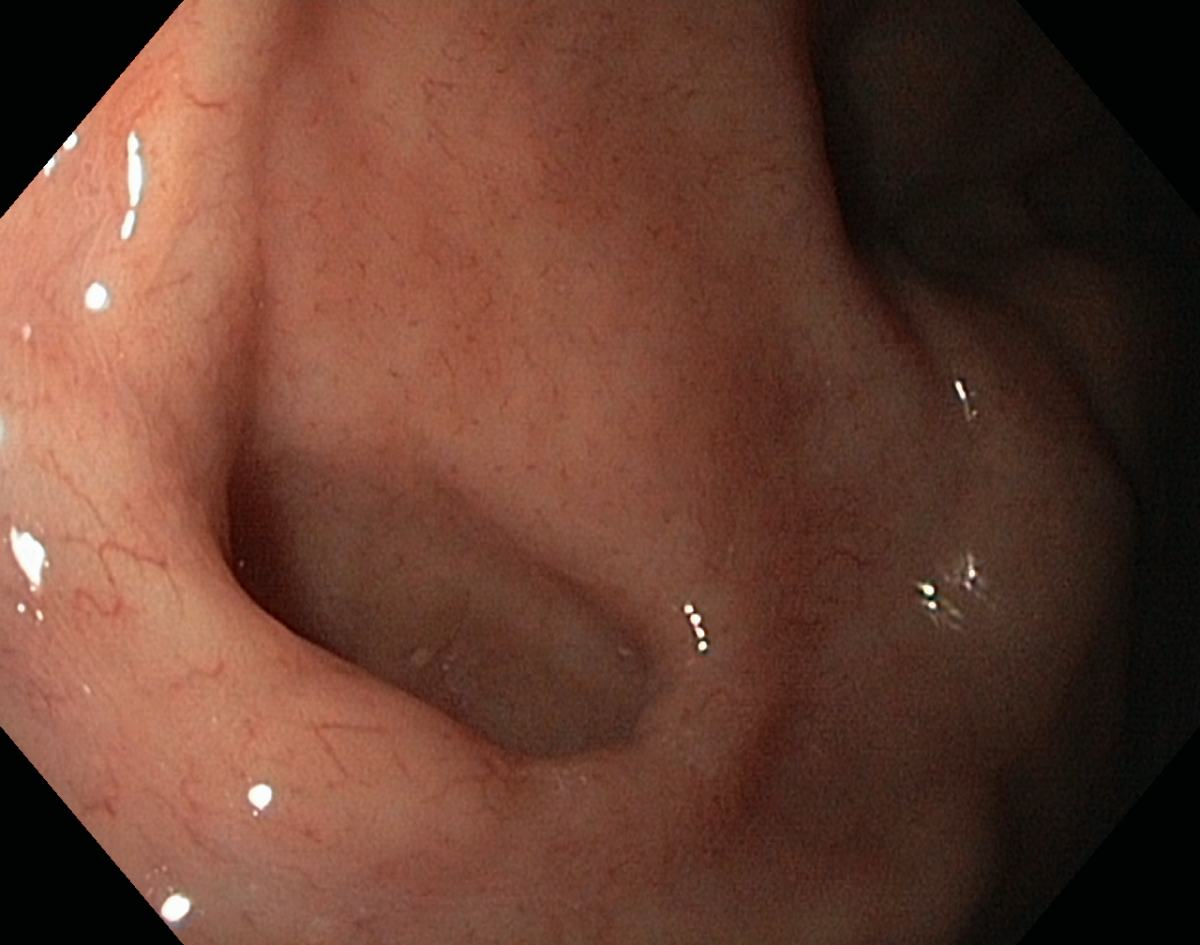

A Normal Gastric Fundus

A normal gastric fundus. Just click on a picture!